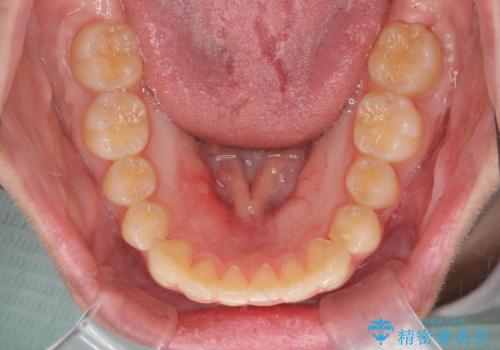

前歯のねじれをマウスピース矯正で治したい

- 前歯のねじれや がたつきを治したい、マウスピース矯正治療を希望され来院されました。

初診時程度のがたつきやねじれであれば、26枚以下のマウスピース矯正 モデレートプランで、比較的リーズナブルに矯正治療を受けていただくことができます。

実際の治療期間は約半年で仕上がりのような綺麗な歯並びを手に入れることができました。